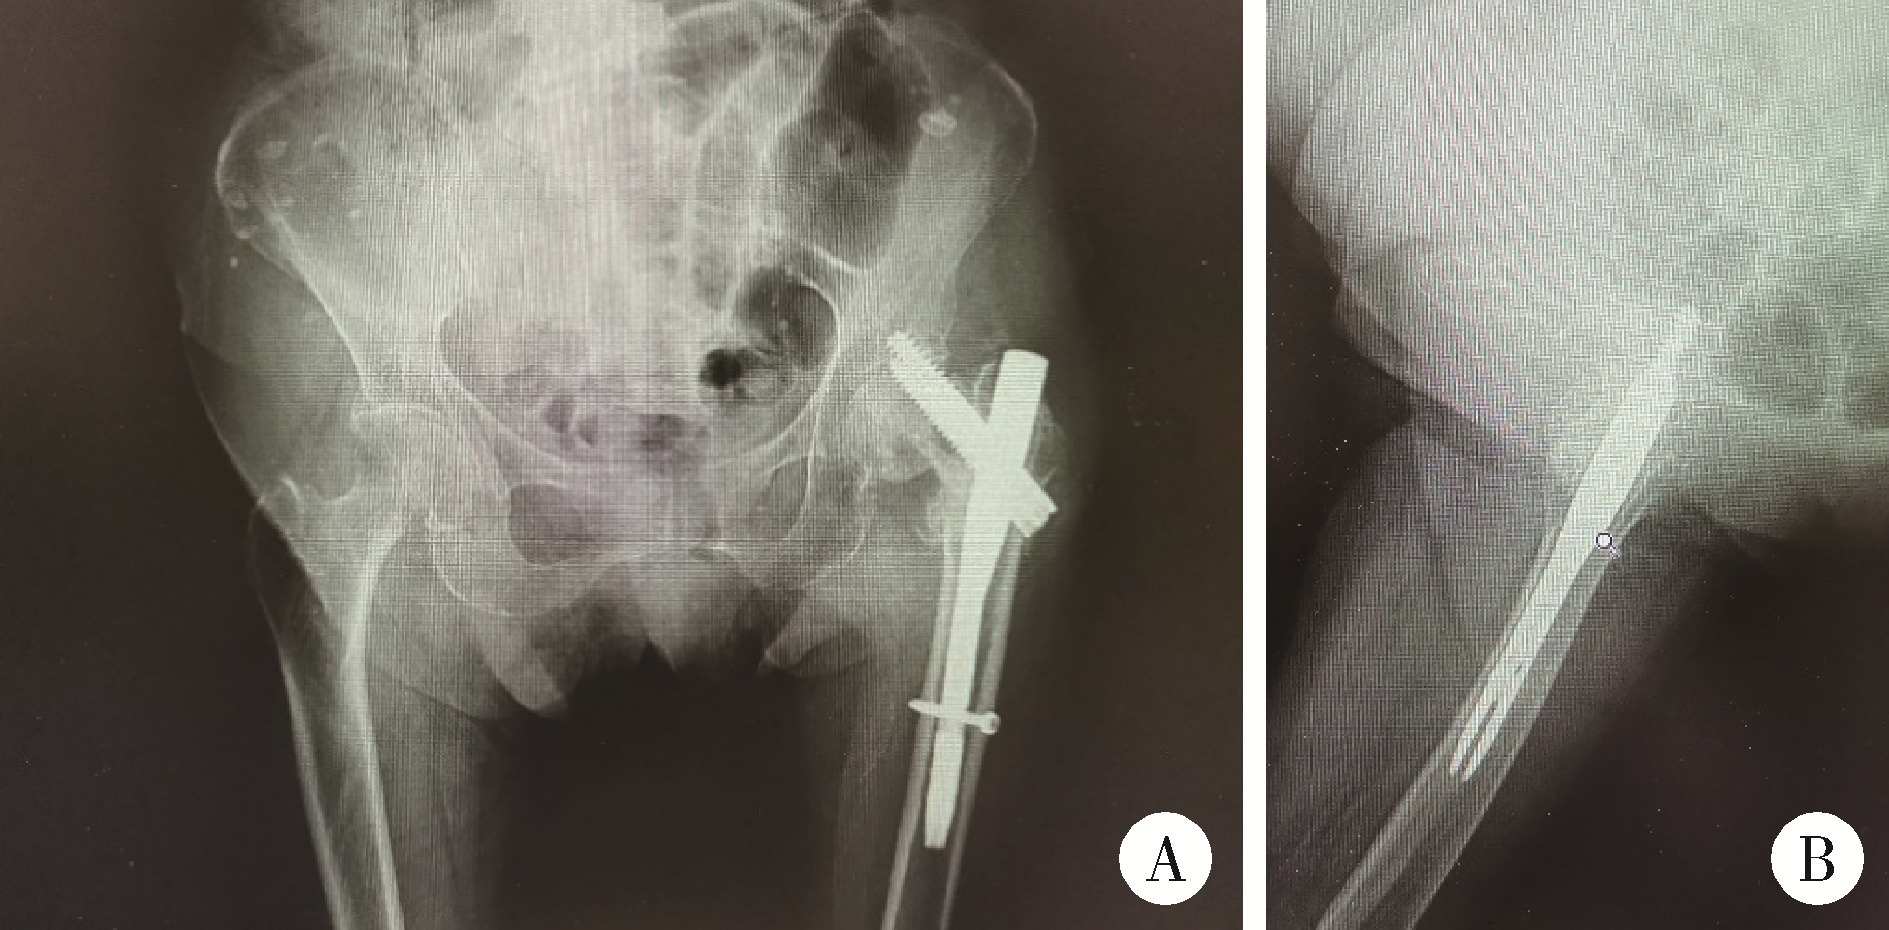

图4 患者术后16个月髋部X线片

Figure 4 Radiographic examination of the hip of patient 16 months postoperatively

A, sixteen months post-operation, X-ray imaging of anteroposterior view of hips; B, lateral view of left hip, revealed a fracture in the left femoral neck and a cut-out screw.